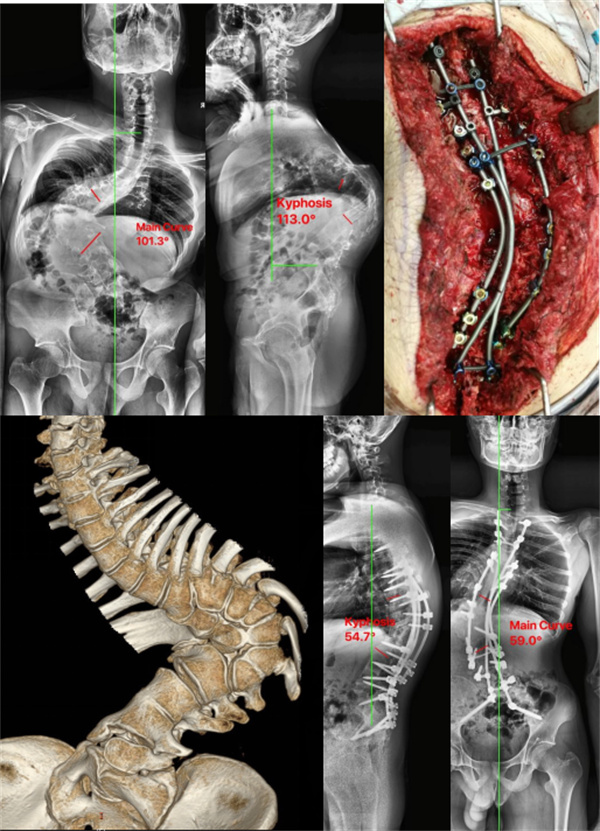

严重先天性脊柱畸形

该患者存在严重的脊柱侧凸及后凸,多节段的半椎体畸形,高危脊髓,椎弓根发育异常,置钉困难,同时需要高级别截骨矫正严重的侧凸及后凸,最终平衡脊柱。手术时间长,出血多,术中脊髓损伤风险极大,术后感染等风险较大。